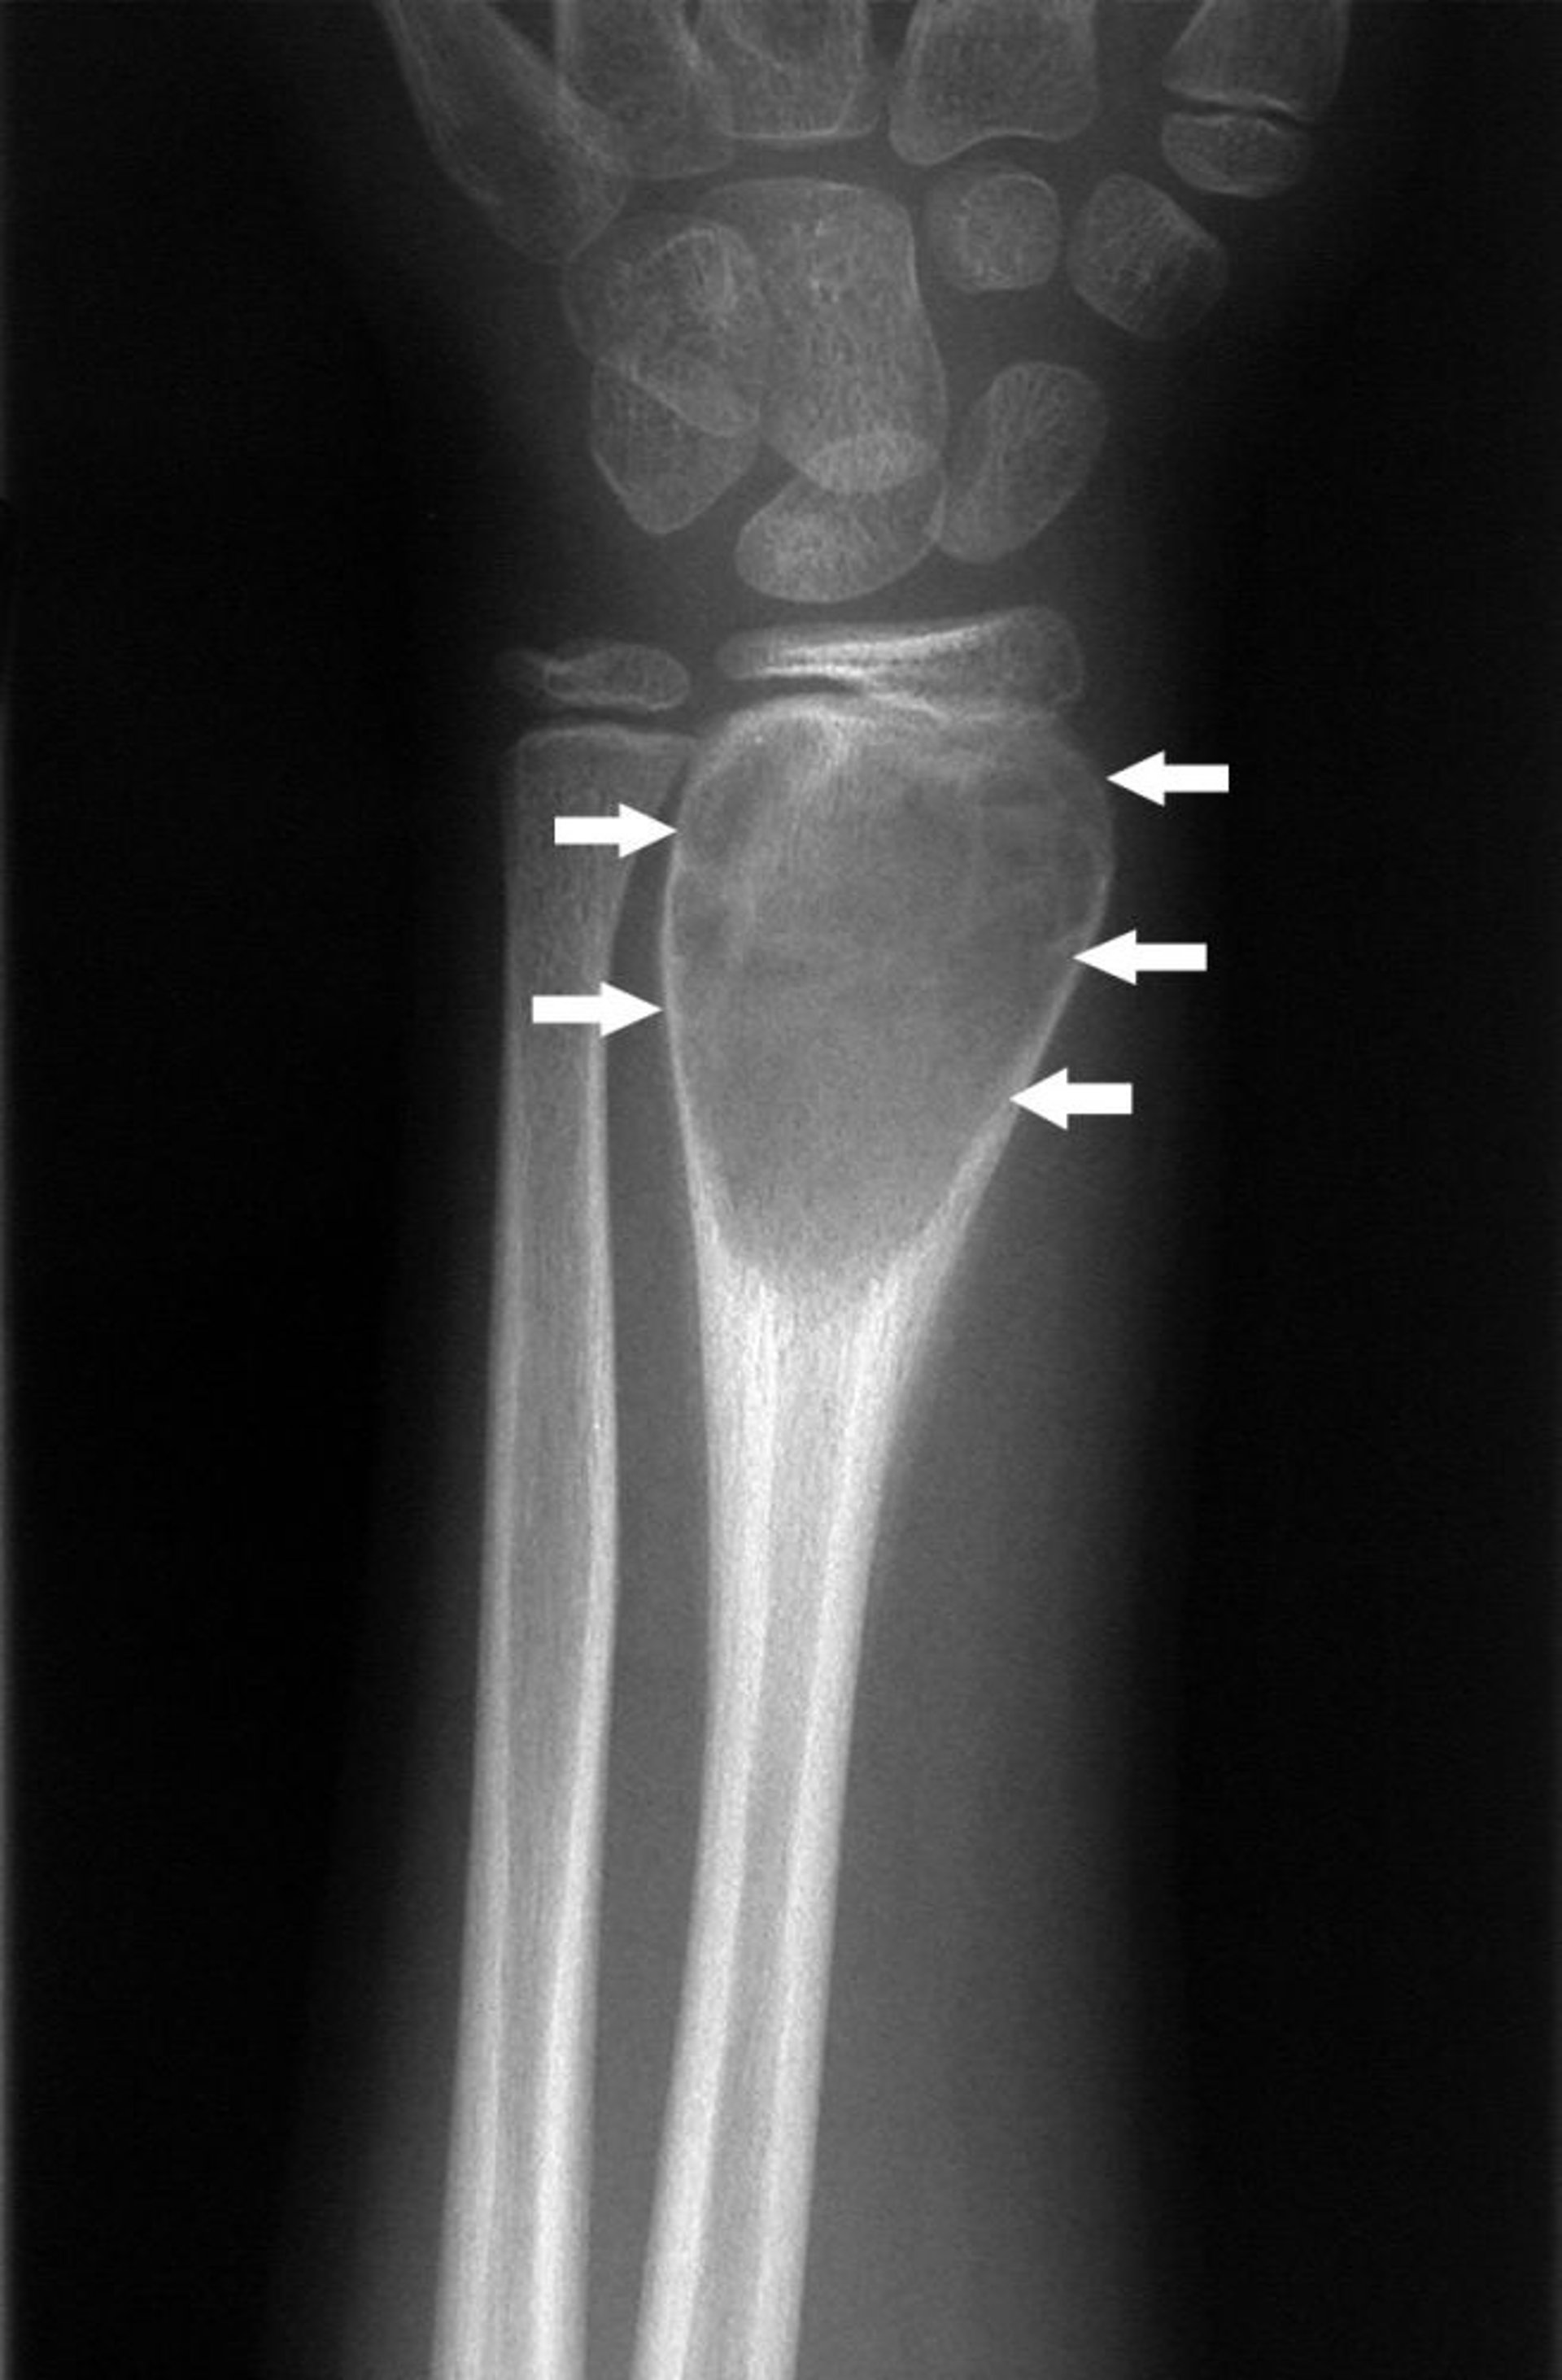

Аневризматическая костная киста запястья

На этой рентгенограмме запястья показана аневризматическая костная киста запястья (стрелки).

Изображение любезно предоставлено д-ром Майклом Дж. Джойсом (Michael J. Joyce) и д-ром Хаканом Иласланом (Hakan Ilaslan).